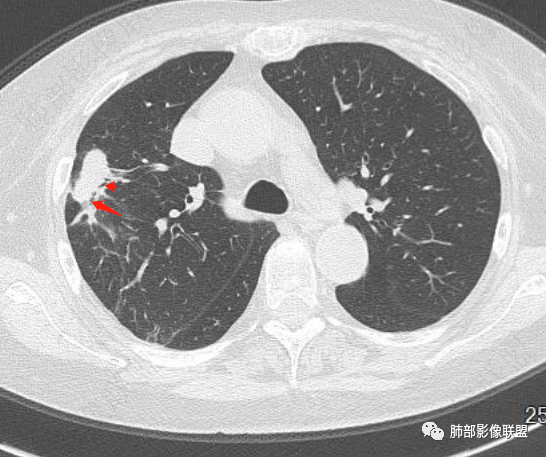

谢加平: 右肺上叶外周,近胸膜下结节病灶,侧向融合,边缘清,见平直边,与胸膜平行分布,支气管进入略扩张,周围见多发长索条影,方向肉芽肿性炎症,建议隐球菌荚膜抗原检查,肿瘤不支持,经皮肺穿刺病理检查!

宇宙: 右肺上叶胸膜下结节,多结节融合,长轴平行胸膜,边缘模糊,周围长索条,胸膜牵拉,近端支气管充气扩张,考虑隐球菌,鉴别OP

衡妈: 老年女性,右肺上叶沿胸膜下不规则实性病灶,长轴平行于胸膜,有结节融合感,边缘部分彭隆部分平直,周围可见数条纤维灶影,病灶内可见充气支气管征未达远端,首诊考虑慢性炎性肉芽肿,隐球菌?机化性肺炎?建议增强扫描及ct下穿刺活检。

放射线 (王秀仙): 右肺上叶胸膜下结节样影,边缘平直收缩,胸膜牵拉,支气管进入病灶并扩张,部分支气管进入后阻塞,长轴平行于胸膜,周围可见片状及条索状影,隐球?机化性肺炎?

晨读:女,70,未诉症状。风湿性多肌痛病史,口服强的松等药物治疗。胸部CT:右肺上叶多发不规则斑片影,沿支气管分布,部分病灶侧向融合、平行于胸膜,边缘平直内收为主、部分彭隆,周围模糊晕、可见数条纤维灶影,胸膜牵拉,病灶内可见充气支气管征、管腔不畅,考虑慢性炎症,PC?OP?鉴别腺Ca、SCLC等。

良孑: 右肺胸膜下多发结节,长轴与胸膜平行,部分病灶有多结节融合,可见近端支气管充气征,有晕征及晕中软毛刺,长期口服激素病史,抗炎效果欠佳。病灶形态单一,无播散性树芽,结节内无支气管穿行,单侧发病,收缩力差,可排除TB,OP及淋巴瘤,综和考虑支持隐球菌

南边: 这个病例大方向没问题,炎性。目前大家都是考虑:隐球菌病、OP,其实这两个结论有重叠,而且这个病例很值得讨论,可惜,估计没有证实。影像特点:病灶长轴与胸膜平行,侧向融合特点明显,符合隐球菌病,问题是目前的状态,边缘收缩明显

内部支气管扩张,周围少量GGO,而且病灶离开了胸膜,附近长索条影,支持机化的改变